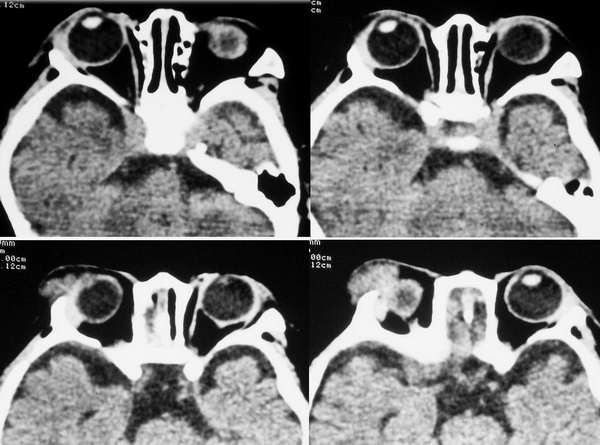

4m发现右眼周外上象限肿物年余 渐增大 软无波动

片不是很清晰,病变位置在外上象限,外直肌中远部增粗,但主要是向外膨胀,边光整,骨质无殊,与颅内无明显相关,以右侧泪腺区占位,混合瘤可能,做增强吧.

泪腺的肿瘤我认为完全可以排除,因为右侧泪腺显示的很好,肿瘤位置较为表浅,位于皮下,和泪腺无明显关系。该肿瘤为来源于软组织的肿瘤,软组织肿瘤种类繁多,影象学的目的更主要的是观察病变的范围和其与临近结构的关系,估计良恶性。该肿瘤边界清楚,与皮肤无粘连,无骨质侵蚀,考虑为良性,以血管瘤和神经纤维瘤的可能性略大些。

首先考虑眼眶毛细胞血管瘤。

横纹肌肉瘤多伴有骨质破坏,本例也应考虑无骨质破坏的横纹肌肉瘤。